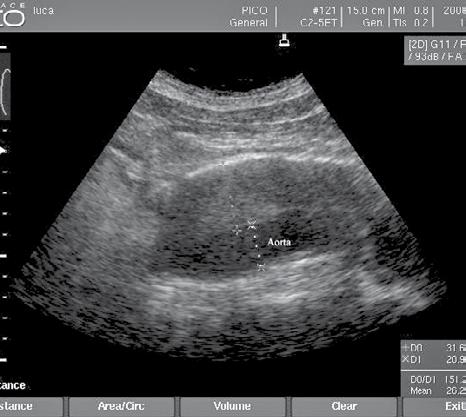

• contractilitatea globală a ventriculului stâng, identificând mărimea și statusul contractil – prezența unei insuficiențe cardiace acute (fig.2) cu necesitatea administrării medicației diuretice, inotrope, vasoactive în funcție de parametrii hemodinamici și corelarea cu aspectul plămânului și a venei cave; vizualizarea unui ventricul stâng hiperkinetic, cu reducerea volumui cavității (fig.3) ceea ce indică corelat cu aspectul VCI cu diametru redus (fig.4) o stare de hipovolemie ce necesită administrarea de fluide;

• aprecierea mărimii ventriculului stâng comparativ cu cel drept – identificarea unei supraîncărcări a ventriculului drept, cu suspiciunea de cord pulmonar acut (fig.5) și necesitatea de administrare de trombolitic pentru trombembolism pulmonar;

Fig.9. Pseudoanevrism aortic Fig.10. Anevrism aortic trombozat Fig.11. Tromboză venă femurală dreaptă

Fig.4. Secțiune intercostală dr. venă cavă inferioară